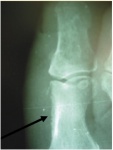

Рис. 1. Типичная картина нейроостеоартропатии (в полном соответствии с С.А. Рейнбергом)

Рис. 2. Динамика развития стопы Шарко

On the far left, a normal radiograph in the acute stage of Charcot.

Слева – нормальная рентгенограмма в острой стадии Шарко.

Subsequently progressive Charcot neuro-osteoarthropathy is seen with dislocation of the Lisfranc joint.

В дальнейшем видно прогрессирование нейро-остеоартропатии Шарко с подвывихом в суставе Лисфранка.